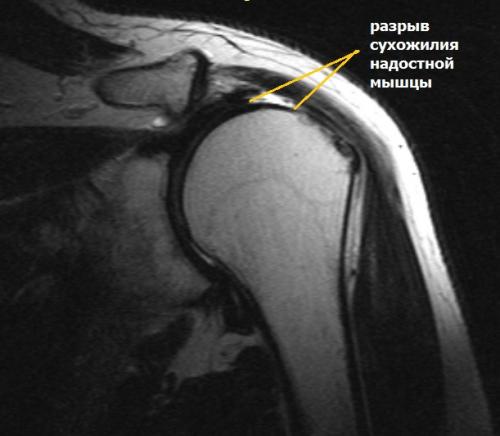

Сужение пространства между акромионом и головкой плечевой кости (импинджмент-синдром) возникает на фоне особого строения акромиального отростка или после получения травмы. Сухожилие надостной мышцы, проходящее в данном пространстве, попадает как бы в тиски и постепенно сдавливается.

Симптомы разрыва вращательной манжеты.

Небольшие разрывы или частичные повреждения могут проходить бессимптомно. Но чаще всего ведущим признаком является боль. При факте травмы боль возникает резко, а при повторяющихся нагрузках она усиливается постепенно и со временем нарастает. Наибольшая интенсивность боли определяется при отведении руки по дуге от 600до 1200. Периодически боль усиливается ночью и приводит к нарушению сна.

Во время осмотра можно выявить снижение силы мышц травмированной конечности. Болевые ощущения ограничивают объем движений в плечевом суставе и приводят к развитию контрактуры (тугоподвижности).